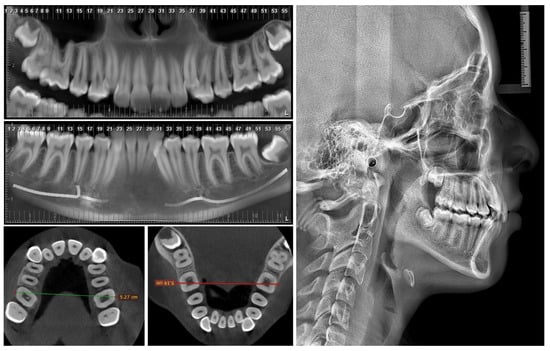

2. Case Report